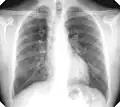

There are three key elements to the diagnosis of silicosis. First, the patient history should reveal exposure to sufficient silica dust to cause this illness. Second, chest imaging (usually chest x-ray) that reveals findings consistent with silicosis. Third, there are no underlying illnesses that are more likely to be causing the abnormalities. Physical examination is usually unremarkable unless there is complicated disease. The examination findings are not specific for silicosis.[20]

For uncomplicated silicosis, chest x-ray will confirm the presence of small (< 10 mm) nodules in the lungs, especially in the upper lung zones. Using the ILO classification system, these are of profusion 1/0 or greater and shape/size "p", "q", or "r". Lung zone involvement and profusion increases with disease progression. In advanced cases of silicosis, large opacity (> 1 cm) occurs from coalescence of small opacities, particularly in the upper lung zones.

With retraction of the lung tissue, there is compensatory emphysema. Enlargement of the hilum is common with chronic and accelerated silicosis. In about 5–10% of cases, the nodes will calcify circumferentially, producing so-called "eggshell" calcification. This finding is not pathognomonic (diagnostic) of silicosis. In some cases, the pulmonary nodules may also become calcified.

Chest X-ray showing uncomplicated silicosis